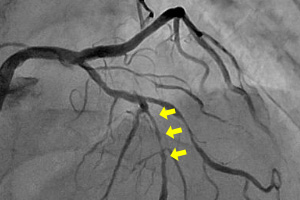

冠動脈(左冠動脈)造影検査

治療前